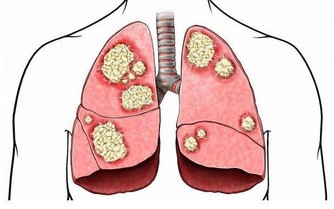

【肺點】功能:改善呼吸,加強身體排毒

肺點位在耳朵正中,軟骨旁的耳孔中央處,用姆指腹輕按2-3次,

有消除皮膚暗沉、黑斑、水腫的效果。